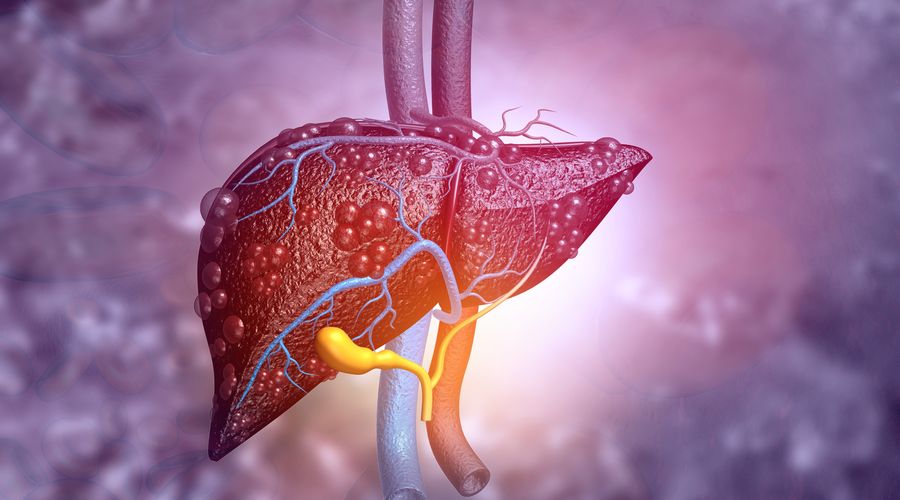

Karaciğer yağlanması, sıklıkla göz ardı edilen bir sağlık sorunudur. Bu durum, siroz gibi ciddi hastalıklara yol açabilir.

Karaciğer yağlanması, günümüzde yaygın bir sağlık sorunu olarak karşımıza çıkıyor. Özellikle yaşam tarzı değişiklikleri ve beslenme alışkanlıkları bu durumu etkileyebiliyor.

Bu durum, karaciğerin normalden fazla yağ biriktirmesiyle ortaya çıkar. Eğer tedavi edilmezse, ilerleyerek siroza dönüşme riski taşır.